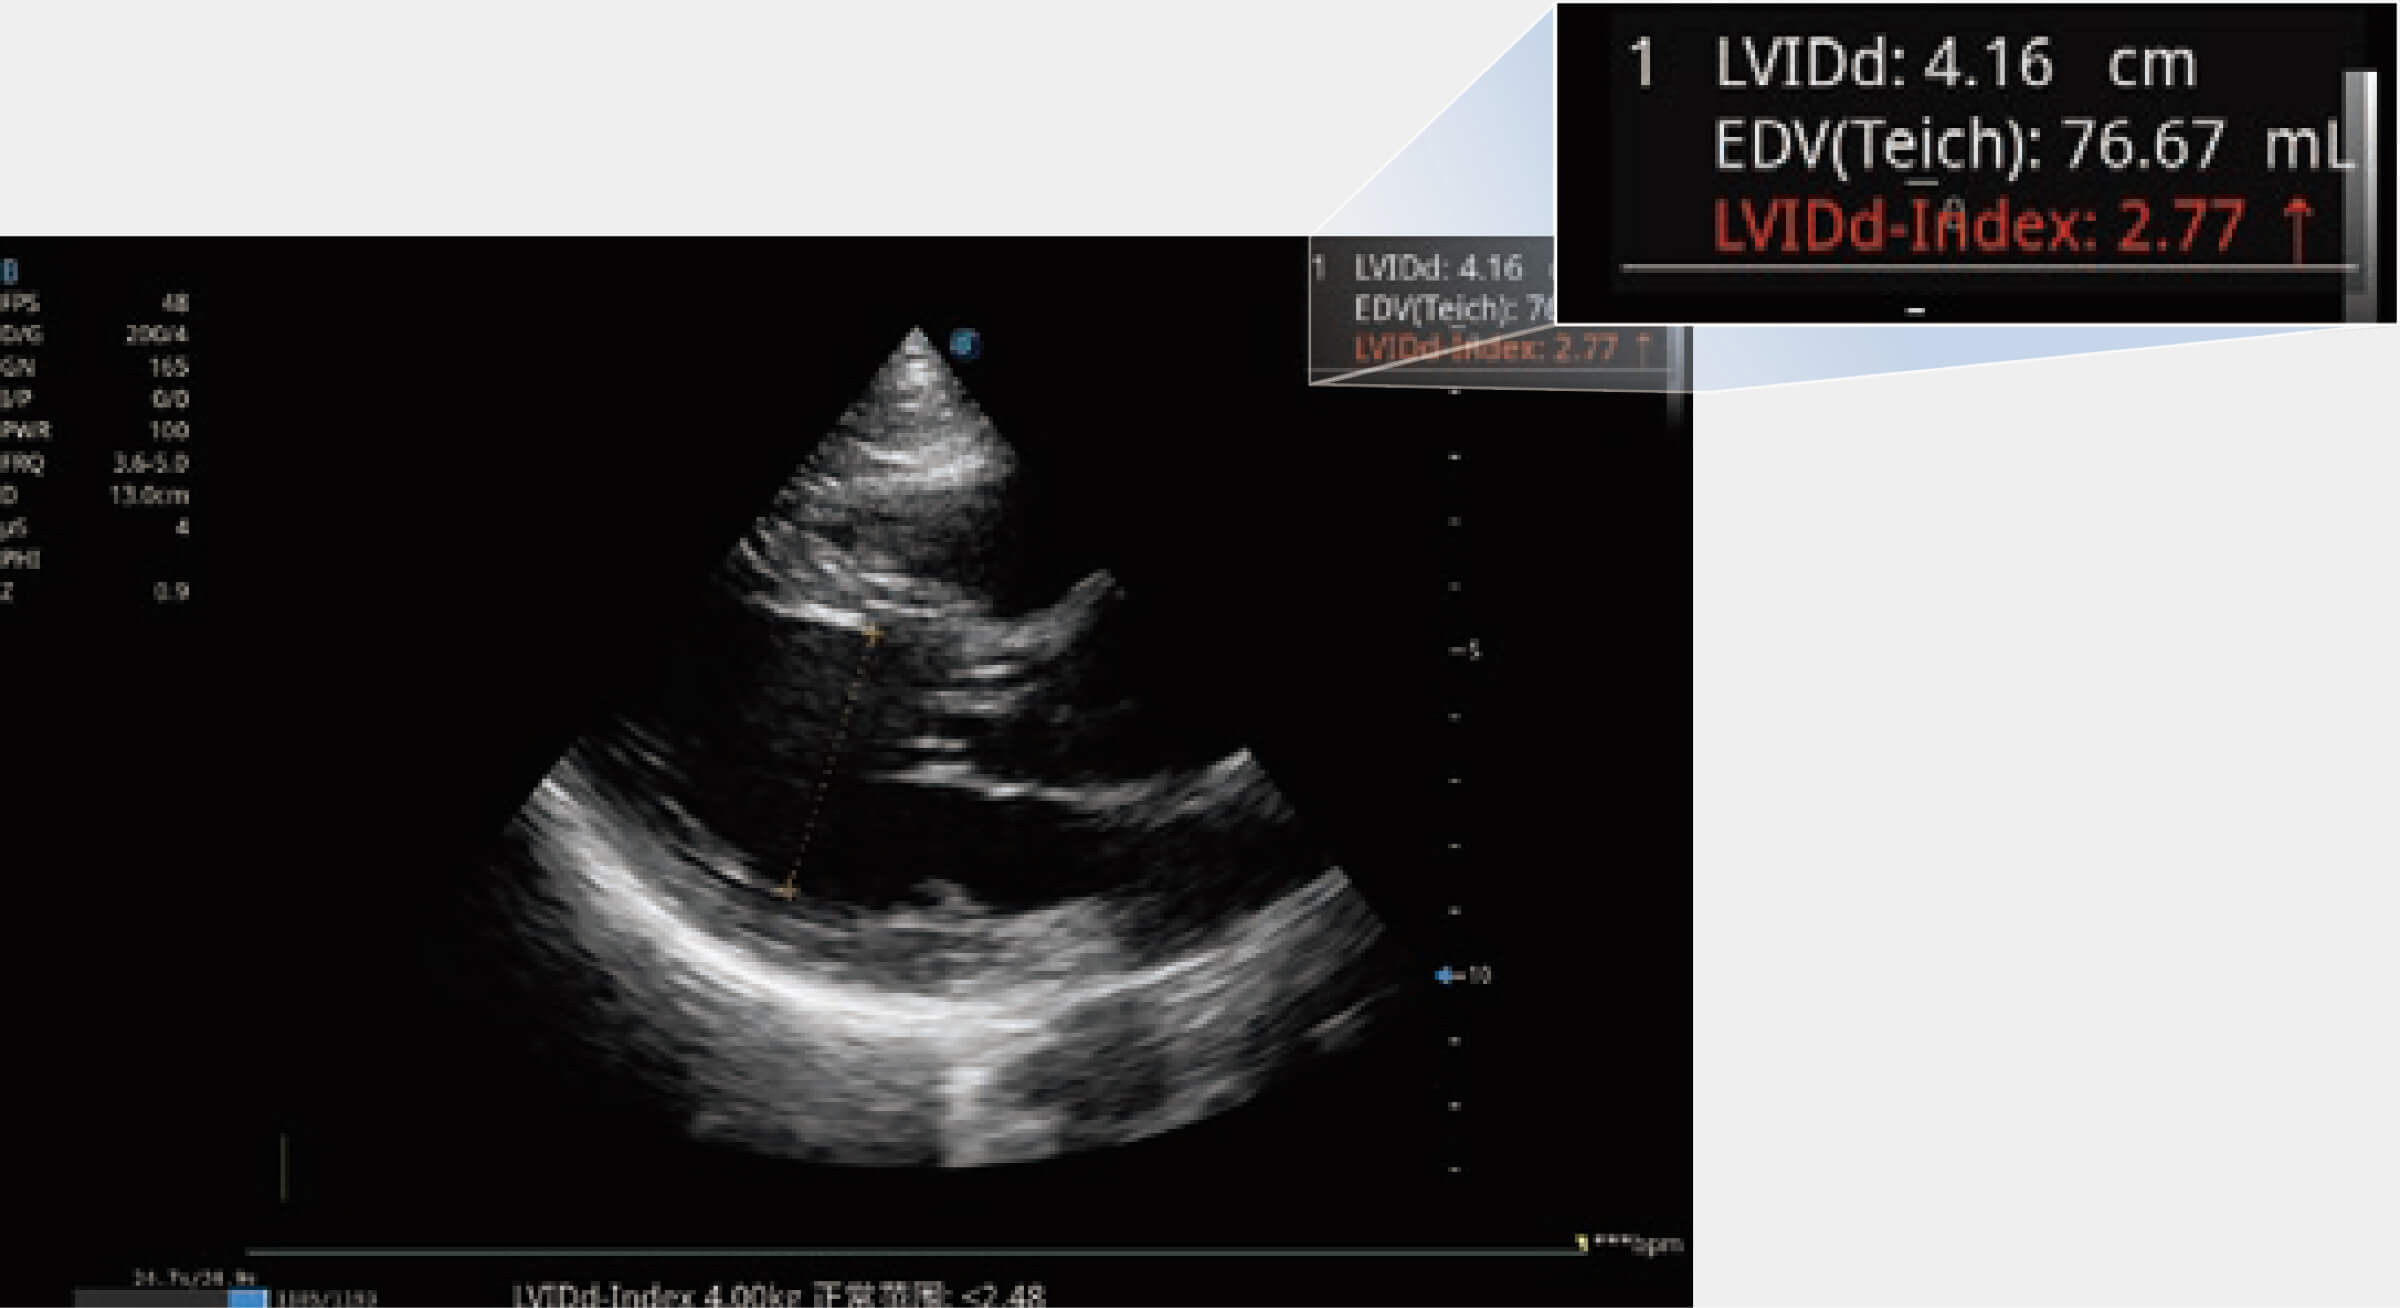

當(dāng)心臟測(cè)量結(jié)果超出正常范圍時(shí),可實(shí)時(shí)預(yù)警提示動(dòng)物醫(yī)生,減少疾病漏診概率。

ProPet 70專(zhuān)為動(dòng)物醫(yī)生設(shè)計(jì),對(duì)不同的動(dòng)物體型和生理結(jié)構(gòu)作出了針對(duì)性的優(yōu)化。通過(guò)動(dòng)物影像專(zhuān)用軟件,可滿足個(gè)性化的應(yīng)用需求,幫助動(dòng)物醫(yī)生獲得更精確的診斷數(shù)據(jù)。